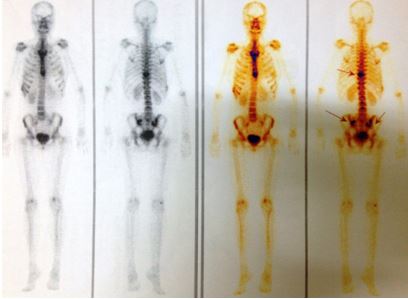

1. Xạ hình xương:

• Tăng hoạt độ phóng xạ tại đốt sống ngực 10, khớp cùng chậu hai bên (hình 5)

Hình 5: Trên xạ hình xương thấy hình ảnh tăng hoạt độ phóng xạ (đầu mũi tên) tại đốt sống ngực 10 và khớp cùng chậu hai bên.

1. Xạ hình xương (sau 5 tháng điều trị): Tăng hoạt độ phóng xạ tại đốt sống ngực số 10, cung trước xương sườn 9,10; xương chậu bên trái (đầu mũi tên hình 11)

Hình 11: Xuất hiện thêm tổn thương xương sườn trên xạ hình xương (bệnh nhân bị va đập vào vùng mạn sườn phải do tai nạn trước khi làm xét nghiệm xạ hình xương)

Xạ hình xương trước điều trị: tăng hoạt độ phóng xạ (đầu mũi tên) tại đốt sống ngực 10 và khớp cùng chậu hai bên

Xạ hình xương sau điều trị: Tăng hoạt độ phóng xạ tại đốt sống ngực số 10, cung trước xương sườn 9,10; xương chậu bên trái (đầu mũi tên hình 11).

Hình ảnh tăng hoạt độ phóng xạ tại cung trước xương sườn 9,10 tương ứng với vị trí va đập trước khi làm xạ hình xương (vòng tròn vàng).